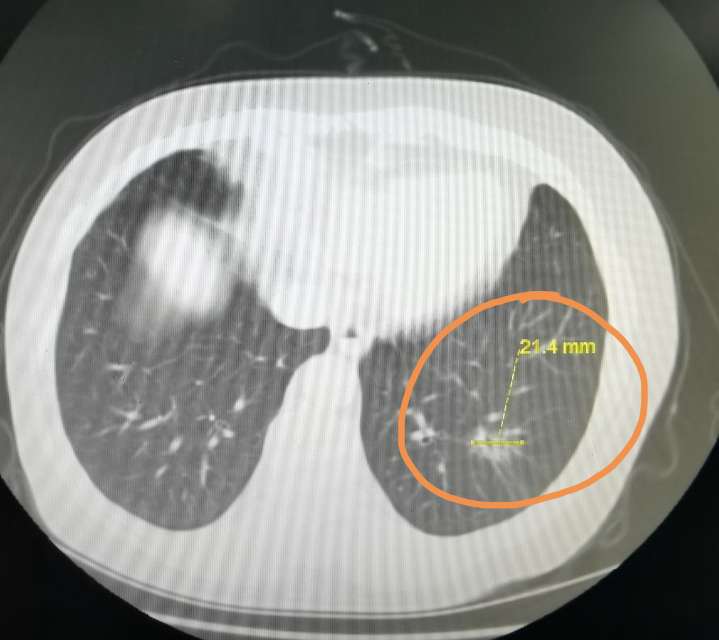

刘懿博士说肺癌(三六二〇)输尿管恶性肿瘤住院,发现肺磨玻璃结节_刘懿

无法楔形活检而行左肺上叶切除,术后送检组织病理诊断未见肿瘤性病变